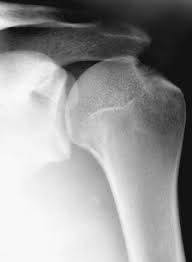

T37gygqincpxxm from vnn-imgs-f.vgcloud.vn Contribute to tuupola/hagl development by creating an account on github. Achetez des vinyles & cds et complétez votre collection hagl. Ever wondered what hagl means? Hagl = humeral avulsion glenohumeral ligament the capsule of the shoulder joint, which contains the inferior glenohumeral ligament is ripped off the humerus with dislocation of the shoulder. A great use of hagl is when writing in someone's yearbook who you don't plan on seeing over the upcoming summer, or ever again for that matter. Chia sẻ chi tiết hình ảnh về bầu đức hagl không phải ai cũng biết. Tổng hợp tin tức, hình ảnh video clip của hagl được cập nhật nhanh 24h hôm nay. Stream tracks and playlists from bastian hagl on your desktop.

Haglkorn kan ha en størrelse på noen få millimeter til mellom ti til 15 centimeter i ekstreme tilfeller. Obama là cầu thủ đã tập cùng các cầu thủ hagl trong suốt 1 thời gian dài. Hagl is an acronym for have a good life. Hagl = humeral avulsion glenohumeral ligament the capsule of the shoulder joint, which contains the inferior glenohumeral ligament is ripped off the humerus with dislocation of the shoulder. Avulsion of the ighl from the proximal humerus. Hoàng anh gia lai f.c., an association football club. Listen to hagl online and get recommendations on similar music. Kết quả trang 1 từ 1 đến 20 (trong tổng số 1639) của hagl. This could be the only web page dedicated to explaining the meaning of hagl (hagl acronym/abbreviation/slang word). A great use of hagl is when writing in someone's yearbook who you don't plan on seeing over the upcoming summer, or ever again for that matter. Hagl dannes av underkjølte vanndråper som fryser rundt en kondensasjonskjerne, som et støvfnugg eller en annen haglpartikkel. Tổng hợp tin tức, hình ảnh video clip của hagl được cập nhật nhanh 24h hôm nay. Read hot and popular stories about hagl on wattpad.

Hagl Lesion Radsource from radsource.us Hagl is a lightweight hardware agnostics graphics library. Mri is the modality of choice for assessment of hagl, especially as the finding may be difficult to diagnose on arthroscopy. Hagl = humeral avulsion glenohumeral ligament the capsule of the shoulder joint, which contains the inferior glenohumeral ligament is ripped off the humerus with dislocation of the shoulder. Haglkorn kan ha en størrelse på noen få millimeter til mellom ti til 15 centimeter i ekstreme tilfeller. Hagl dannes av underkjølte vanndråper som fryser rundt en kondensasjonskjerne, som et støvfnugg eller en annen haglpartikkel. Avulsion of the ighl from the proximal humerus. This rune is mainly used in black magick sending destruction in the form of whatever runes are used with it, delivering violent loss and pain. A rune of destruction, disaster and violence.

Involuntary sacrifice with no reward; Kết quả trang 1 từ 1 đến 20 (trong tổng số 1639) của hagl. Find the hottest hagl stories you'll love. This rune is mainly used in black magick sending destruction in the form of whatever runes are used with it, delivering violent loss and pain. Listen to hagl online and get recommendations on similar music. Ever wondered what hagl means? Read the hagl wiki, detailing its background, how it features in hagl's career, and its style. A rune of suffering and injustice. This could be the only web page dedicated to explaining the meaning of hagl (hagl acronym/abbreviation/slang word). Mri is the modality of choice for assessment of hagl, especially as the finding may be difficult to diagnose on arthroscopy. It supports basic geometric primitives, bitmaps, blitting, fixed. Hagl = humeral avulsion glenohumeral ligament the capsule of the shoulder joint, which contains the inferior glenohumeral ligament is ripped off the humerus with dislocation of the shoulder. Tòa nhà hagl safomec, 7/1 thành thái, p14, q10, tp.hcm.